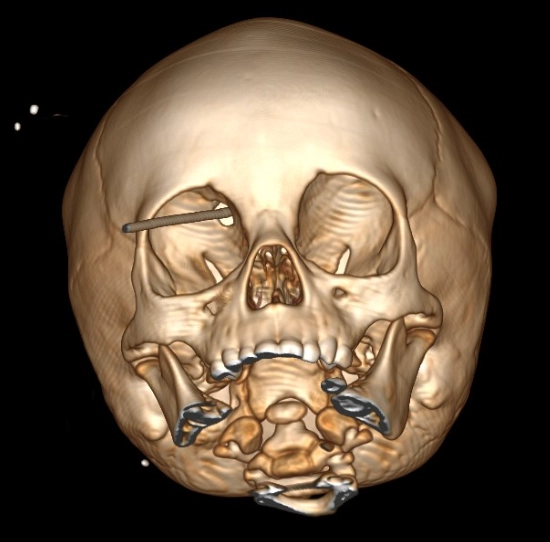

Tổn thương xuyên thấu sọ não vận tốc thấp (Low-velocity penetrating brain injury)

16/03/2026